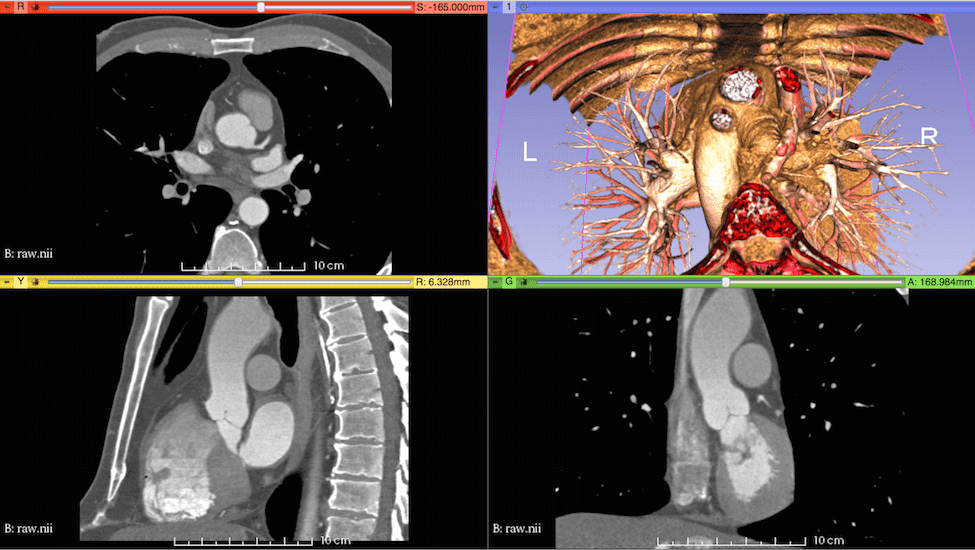

A three-dimensional representation of the aortic root and ascending aorta was generated from publicly available medical image data. This study uses one of the sample data sets from the OsiriX DICOM Image Library that consists of three-dimensional computed tomography angiography (CTA) of an anonymous patient’s chest following administration of a contrast agent. The use of a contrast agent enables better discrimination of the blood vessels and heart chambers than non-contrast CT images. The image data were acquired at the Ronald Reagan University of California at Los Angeles Medical Center in Santa Monica, CA using a Siemens SOMATOM Sensation 16 CT scanner. The image resolution is 512512355 with a voxel size of 0.470.470.5 mm. The image was processed by an anisotropic diffusion filter to mitigate noise. Sample renderings of the patient data are shown in Fig. 1.

The aortic root and ascending aorta were segmented by a semi-automated method implemented in the ITK-SNAP software. ITK-SNAP [43, 44], which is based on the Insight Segmentation and Registration Toolkit (ITK) [45, 46], provides a graphical interface for the implementation of the active contour model, also known as Kass snakes [47], for semi-automatic segmentation. The algorithm works by minimizing an energy functional that is determined by voxel intensities. The generated segmentation is shown in Fig. 2.